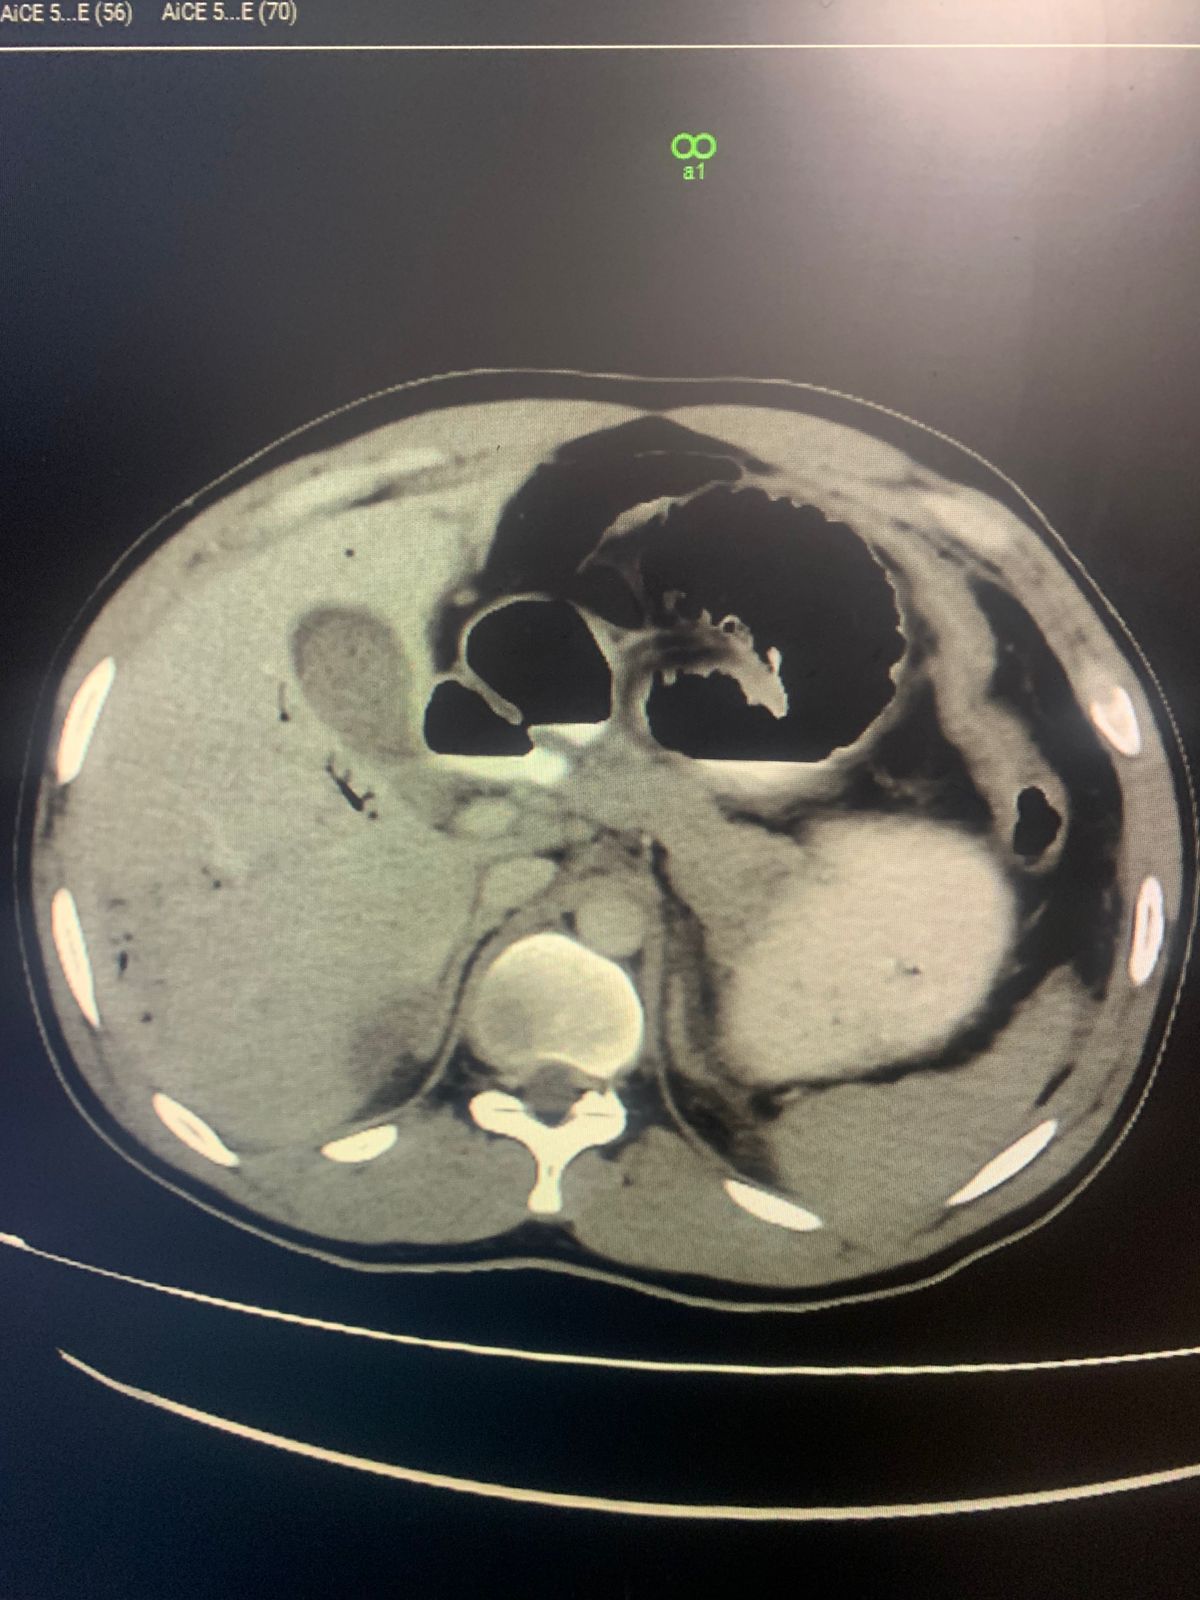

Young Male with Gunshot Injury Contributed by the Department of Radiology JPMC, Karachi

CT abdomen with IV and per rectal contrast

Findings :

. Bowel (sigmoid colon)perforation with leakage of contrast and Pneumoperitonium

. Moderate free fluid

. Portal venous gas

. Pseudoaneurysm of right external iliac artery

. Mild Bilateral pleural effusion